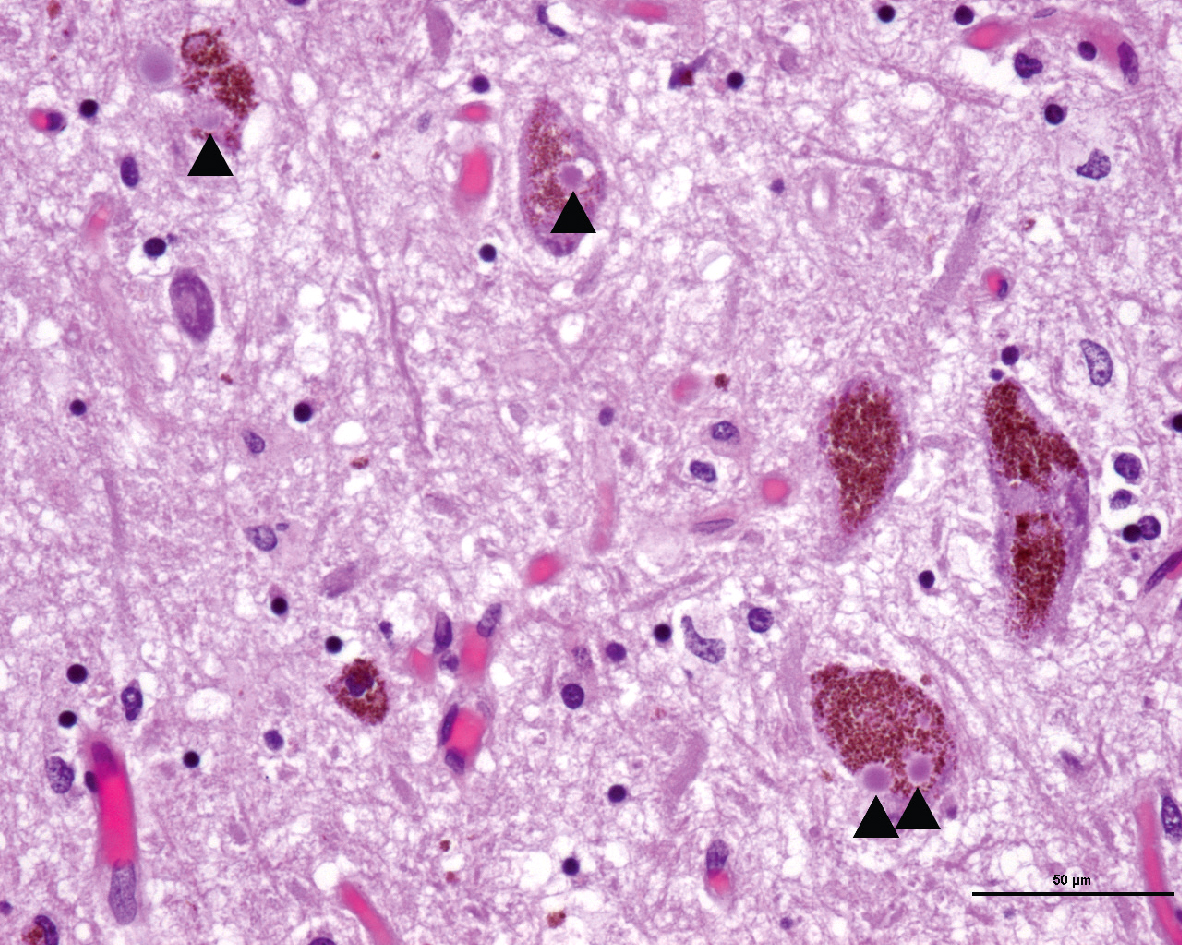

• Présence de corps de Lewy (inclusions intraneuronales contenant des agrégats anormaux d’alpha-synucléine) (fig. 17.1).

Fig. 17.1

Plusieurs corps de Lewy (flèches noires) sont observés dans des neurones dopaminergiques de la substance noire compacte chez ce patient atteint d’une maladie de Parkinson.Dans cette image, nous observons plusieurs corps de Lewy (indiqués par des flèches noires) présents dans des neurones dopaminergiques de la substance noire compacte chez un patient atteint de la maladie de Parkinson. Les corps de Lewy sont des agrégats anormaux de protéines qui se forment à l'intérieur des cellules nerveuses. Ils sont principalement composés d'alpha-synucléine, une protéine qui, lorsqu'elle s'accumule de manière anormale, est associée à la dégénérescence neuronale. La substance noire compacte est une région du cerveau qui joue un rôle crucial dans le contrôle des mouvements, et les neurones dopaminergiques de cette région sont particulièrement vulnérables dans la maladie de Parkinson. La présence de corps de Lewy dans ces neurones est un marqueur pathologique caractéristique de cette maladie neurodégénérative. La maladie de Parkinson se manifeste par des symptômes moteurs tels que des tremblements, une rigidité musculaire et des difficultés à initier des mouvements, en grande partie dus à la perte de neurones dopaminergiques dans la substance noire compacte. L'observation de corps de Lewy dans cette région du cerveau aide à confirmer le diagnostic de la maladie de Parkinson et à mieux comprendre les mécanismes sous-jacents de cette pathologie.